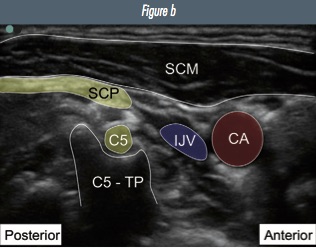

From the level of the cricoid cartilage, identify the interscalene groove and brachial plexus. Scan cranially and observe the C6 and then C5 nerve roots move deep towards their respective transverse processes (see interscalene chapter for images). At the level of the C5 transverse process, the superficial cervical plexus can be seen superficially as a line of hyperechoic beads in the fascial plane deep to the SCM muscle.

Figure 2: Ultrasound image of a) superficial cervical plexus b) annotated image (CA=carotid artery; IJV=internal jugular vein; C5-TP=C5 transverse process; C5=C5 nerve root; SCP=super cial cervical plexus; SCM=sternocleidomastoid muscle).

Small hyperechoic beads superior and super cial to C5 transverse process, deep to sternocleidomastoid posterior border. May be difficult to visualise the individual nerves.